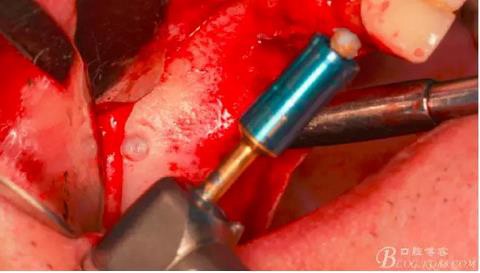

先使用1mm停止環(huán)套在開孔鉆上。

在需要開窗的位置的中心位點垂直骨面鉆入1mm深度。

沒有鉆透,更換2mm停止環(huán)。

轉速800-2000轉,鉆透骨壁,有明顯落空感。有老師質(zhì)疑這么快的轉速會不會刺穿上頜竇膜?請大家放心,絕對不會。